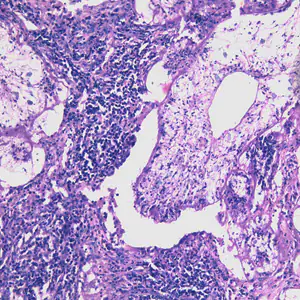

Migrating spargana cause various symptoms depending on the final location in the host. Spargana may locate anywhere, including subcutaneous tissue, breast, orbit, urinary tract, pleural cavity, lungs, abdominal viscera and the central nervous system. The migration in subcutaneous tissues is usually painless, but when spargana settle in the brain or spine a variety of neurological symptoms may occur, including weakness, headache, seizure, and abnormal skin sensations, such as numbness or tingling. If the inner ear is involved, the patient may experience vertigo or deafness. Occasionally, Sparganum proliferum can cause proliferative lesions in the infected tissue, with multiple plerocercoids present in a single site.

Proliferating spargana in lung tissue.